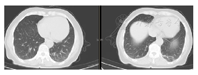

1个月后复查胸部显示左肺实变完全吸收痊愈。

综上,一家四口人,三人发热,两人确诊鹦鹉热,一人临床疑诊鹦鹉热。确诊二人出院1个月后门诊随诊,复查CT肺部实变完全吸收(图3、图4)。